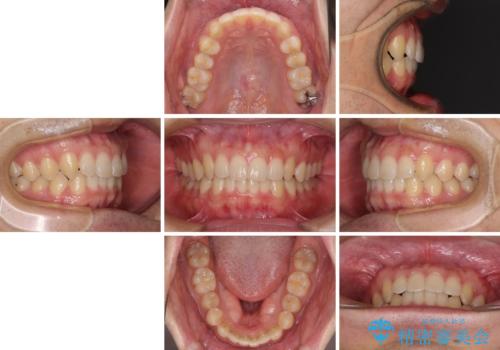

- 上下前歯のデコボコと深い咬み合わせを気にして来院された患者様です。

インビザラインによる上下歯列の拡大と、IPR(歯と歯の間を削る)にるスペースの獲得により、前歯のデコボコとディープバイトを改善することとしました。

もう少し下の前歯を整えたかったのですが、患者様の治療を早く終了させたいという希望により、細かい叢生を残しての終了となりました。